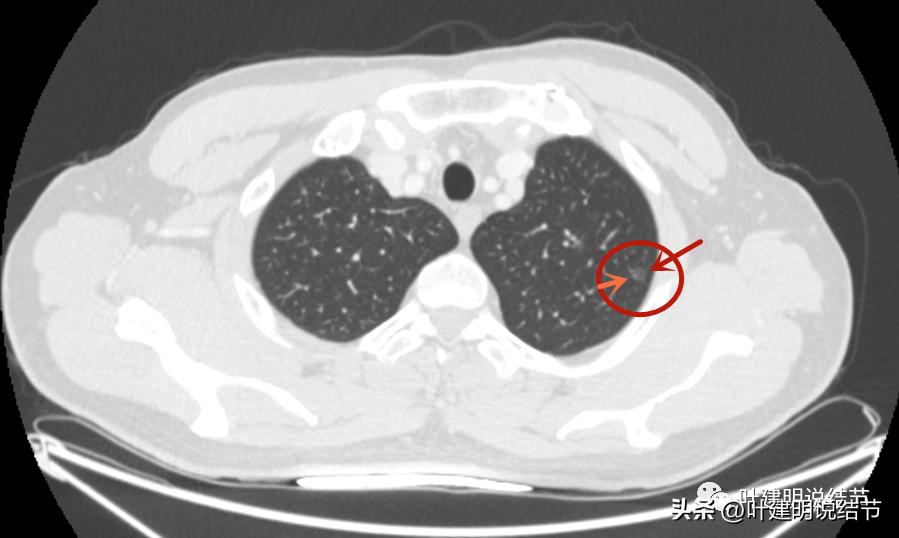

病灶1:左上叶结节

边上有小血管贴着,但病灶本身密度确实低。

病灶血管贴边,瘤肺边界较清。

冠状位见多角度多边有血管贴着,磨玻璃部分密度低,轮廓清。

这两处结节均考虑是肿瘤范畴的,因为轮廓清,磨玻璃密度,并有血管穿行。但整体均还上,密度还很低,尤其左侧的密度更低。这样密度极低的磨玻璃结节,它周围的血管贴边并不似因为肿瘤生长需要富血供,从而吸引了新生血管过来,或周围血管发出分支来供血,而是“碰巧”有血管刚好经过的可能性更大些,且淡磨玻璃密度的结节基本不具有侵袭性,不至于侵犯或影响血管从而带来危险。如果一定要来预估一下病理会是什么,大概左侧以不典型增生可能性大,不能除外原位癌;右侧稍倾向原位癌,但也可能是不典型增生或肺泡上皮增生,至少近期风险低,能随访。

左侧磨玻璃结节红色圈起来的瘤肺边界清,有血管贴边,但整体密度低,没有实性成分,考虑仍是不典型增生或原位癌阶段,近期风险低,个人觉得最好先随访,因为可能很多年不变的,而且也可能再检出新的结节来。况且随访有进展再干预,效果也是一样的。右侧结节也是肿瘤范畴,但风险一样不高,建议同样半年到一年复查(其实1年也关系不大的)。意见供参考!